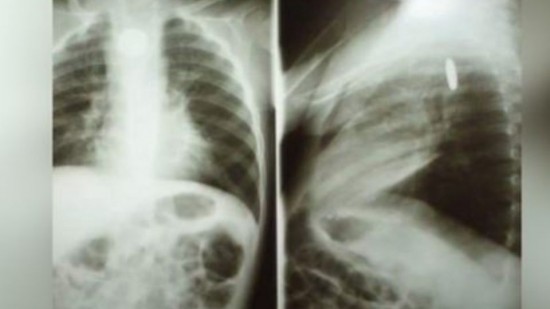

Fue así como le ocurrió a Dylan, un bebé de tan solo dos años de edad, quien actualmente se encuentra luchando por su vida, después de que se tragó por accidente una pila, la cual, al estar compuesta de químicos tóxicos, le provocó daños en el esófago y pulmones.

Además, otra de las consecuencias de haber ingerido la pila es que sufrió daños en el esófago y un pulmón, por lo que requiere que se le hagan estudios constantes, los cuales tendrían un costo de más de cinco mil pesos cada uno, es por eso que, familiares y allegados del pequeño, quien es originario del municipio de Cananea en el estado de Sonora, realizaron una campaña de apoyo mediante sus redes sociales debido a que la atención médica está resultando costosa, por lo que buscan recabar fondos que les ayuden a sostener los gastos hospitalarios.